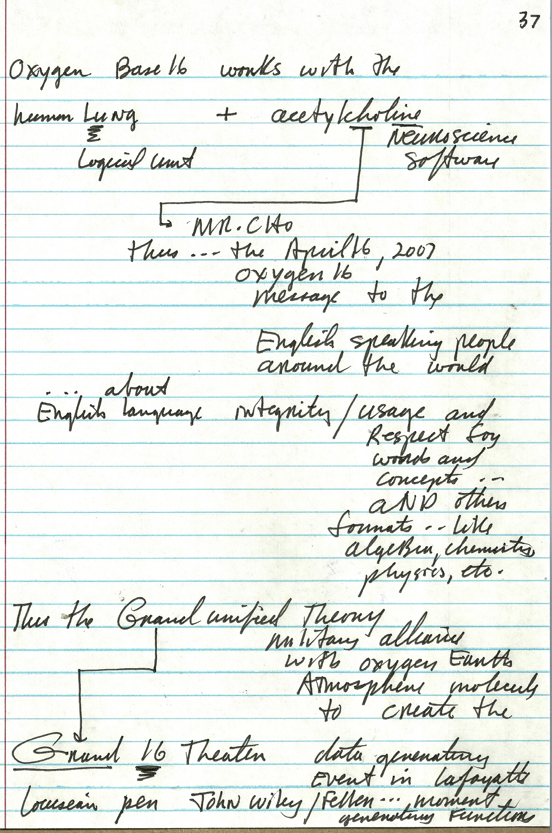

1 acetylcholine neurotransmitter wars

37 Mr. CHO